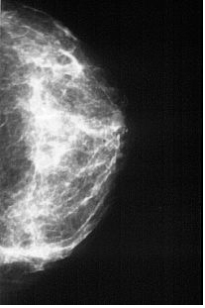

Rachel - The Anthropomorphic Breast Phantom

The ¡°Rachel¡± Anthropomorphic Breast Phantom provides an image with the detail and contrast of an actual mammogram. The phantom may be used for evaluation of the effects of variable conditions encountered in mammography. These include differences machines, varying exposure parameters, processing conditions, and film/screen combination.